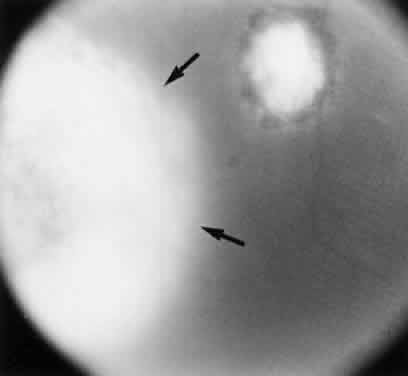

Ocular toxoplasmosis most commonly presents as a focus of necrotizing retinitis (Fig. 7) involving the inner layers of the retina and associated with a whitish fluffy lesion surrounded by retinal edema.6,59 Cells are seen in the vitreous overlying the lesion. The focus of retinitis may be large (Fig. 8) or small (Fig. 9). The retina is the primary site for the multiplying parasites, whereas the choroid and sclera may be the sites of contiguous inflammation. When the choroid is involved by the inflammatory reaction, the lesion is referred to as retinochoroiditis. The organisms are rarely seen in the choroid. The retinal lesion may be small and single or large and multiple and may reach several disc diameters in size. Large granulomas in the posterior segment of the eye frequently are seen in patients with ocular toxoplasmosis (Fig. 10). This is associated with extensive and marked vitreous reaction that precludes visualization of the retina, and the granuloma appears as a yellowish mass surrounded by a red reflex. Punctate outer retinal involvement may be seen in some patients with toxoplasmosis.60 These appear as multifocal, gray-white lesions in the deep retina and at the level of the retinal pigment epithelium accompanied by no overlying vitreous reactions. The lesions may resolve to form fine, granular white dots. This is the earliest finding seen in the rabbit models of ocular toxoplasmosis after the injection of Toxoplasma organisms in the suprachoroidal space. The lesions in the animal model may start as deep outer retinal punctate lesions that later involve the inner layers of the retina and cause the typical focus of retinochoroiditis. Involvement of the macular area is common in patients with congenital toxoplasmosis, and exudative retinal detachment may occur in severe cases. Clumps of inflammatory cells may be seen in the vitreous or over the detached posterior vitreous face. The focus of retinitis may be a manifestation of congenital toxoplasmosis or may be associated with or follow an episode of acquired systemic toxoplasmosis. Patients presenting with recurrent toxoplasmic retinochoroiditis usually are in the second or third decade, but the disorder may occur at any age. Healing of the retinitis is associated with a decrease in retinal edema and flattening of the lesion with evidence of scar formation surrounded by variable amounts of pigment (Fig. 11). The lesion may appear as a punchedout scar with underlying sclera resulting from extensive retinal and choroidal necrosis surrounded by pigment proliferation (Fig. 12), it may become a conglomerate or proliferated retinal pigment cells (Fig. 13), or it may be small and appear as a pigment clump in the retina. The retinochoroiditic scar may harbor the Toxoplasma cysts. Healing also is associated with decrease in the vitreous cells and improvement in visual acuity. Immunologic suppression is associated with recurrence of retinochoroiditis (Fig. 14). Recurrent toxoplasmic retinitis frequently appears as “satellites” or occurs adjacent to a previous scar. Old, inactive lesions often appear to be a conglomeration of previous multiple inflammatory foci (see Fig. 13).

Fig. 10. Large Toxoplasma retinochoroiditic granuloma with vitreous exudates (arrows). The lesion appears as a pale, elevated mass in a background of red reflex. A small punched-out retinochoroiditic scar and fundus details are hazily seen.